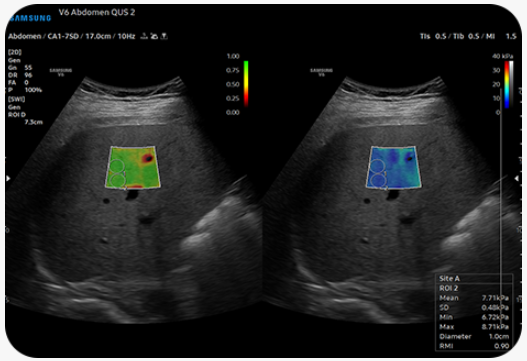

Zobrazení a kvantifikace tuhosti tkáně neinvazivní metodou |

S-Shearwave Imaging™ umožňuje neinvazivní hodnocení tuhých tkání v různých aplikacích. Barevný elastogram, kvantitativní měření, možnosti zobrazení a možnost výběru oblasti zájmu lékařem jsou užitečné zejména pro přesnou diagnostiku onemocnění prsu a jater.